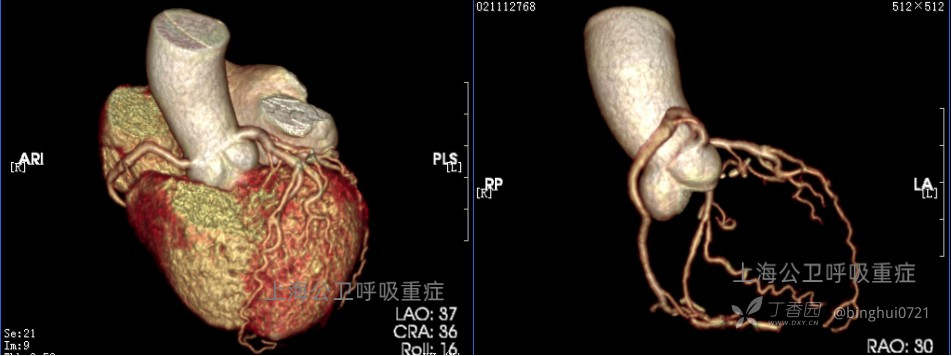

心脏冠脉CTA:未见明显异常。(见图3)

图3